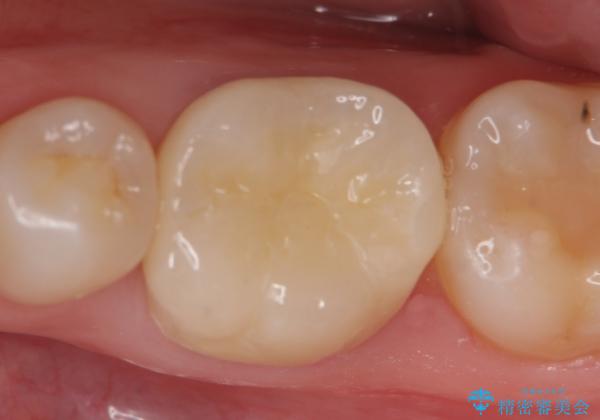

- 他院にて左下6番目の歯の根管治療を行っていたが、痛みが引かず抜歯を提案されたため、何とか歯を残せないかと当院にいらっしゃった方の症例です。

顕微鏡下で精密根管治療を行い、症状の緩解を確認後、オールセラミッククラウンによる補綴を行いました。